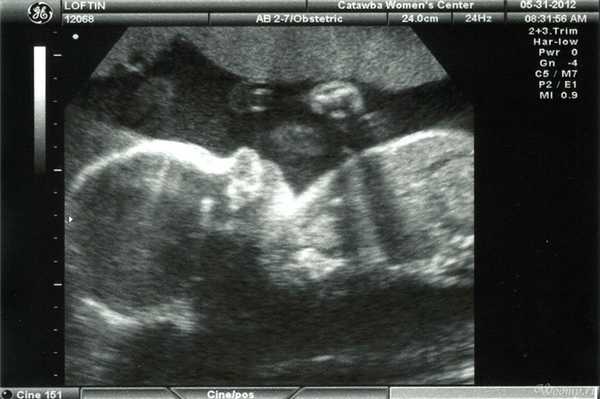

Фото УЗИ ребенка на разных сроках беременности

Если беременность желанная, будущие родители внимательно относятся к пренатальной диагностике плода. Чтобы убедится, что ребенок развивается нормально, в течение 9 месяцев гинеколог несколько раз направляет женщину на ультразвуковое исследование. Фото УЗИ может многое рассказать врачу и будущим родителям о малыше. Кроме того, снимок станет трогательным напоминанием для семейного архива.

Чтобы сделать фото УЗИ малыша на разных сроках, беременной женщине необходимо записаться на ультразвуковой скрининг в медицинском центре «Диана».

Фото УЗИ ребенка на 20 неделе беременности

Этот срок считается переломным, поскольку к 20 неделе сформированы почти все органы и системы. Оставшуюся часть беременности происходит рост организма и набор веса, во многом за счет появления жировой прослойки. На этом сроке назначают проведение второго ультразвукового исследования.

Снимки УЗИ на 20 неделе делают с такими целями:

- оценка развития и функционирования внутренних органов;

- выявление риска хромосомных аномалий;

- определение пола малыша;

- оценка динамики развития и набора веса.